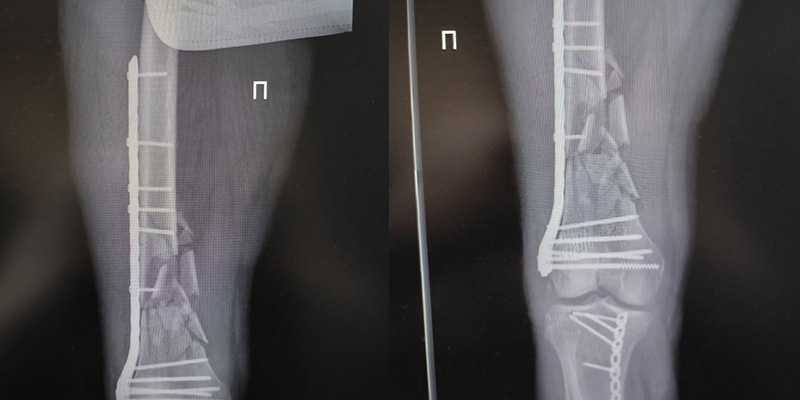

«Пациент с сочетанной травмой был госпитализирован в отделение реанимации, и после стабилизации состояния переведен в трематологию. За трехчасовую операцию мы провели остеосинтез правого бедра и обеих голеней - у мужчины закрытый многооскольчатый перелом нижней трети правой бедренной кости, закрытые оскольчатые переломы большой и малой берцовых костей голеней. Все фрагменты собрали, закрепили пластинами и штифтами – это обеспечивает правильную фиксацию и исключает вероятность вторичного смещения», - уточняет заведующий травматологическим отделением Геннадий Гаврилович Гордеев.

Помимо операции и медикаментозного лечения пациенту потребовалось неоднократное переливание компонентов крови - уровень гемоглобина у него опускался практически вполовину. Как объясняет врач, даже если перелом закрытый, и нет наружного кровотечения, он всегда сопровождается внутренними кровоизлияниями и гематомами, что влечет за собой потерю крови.